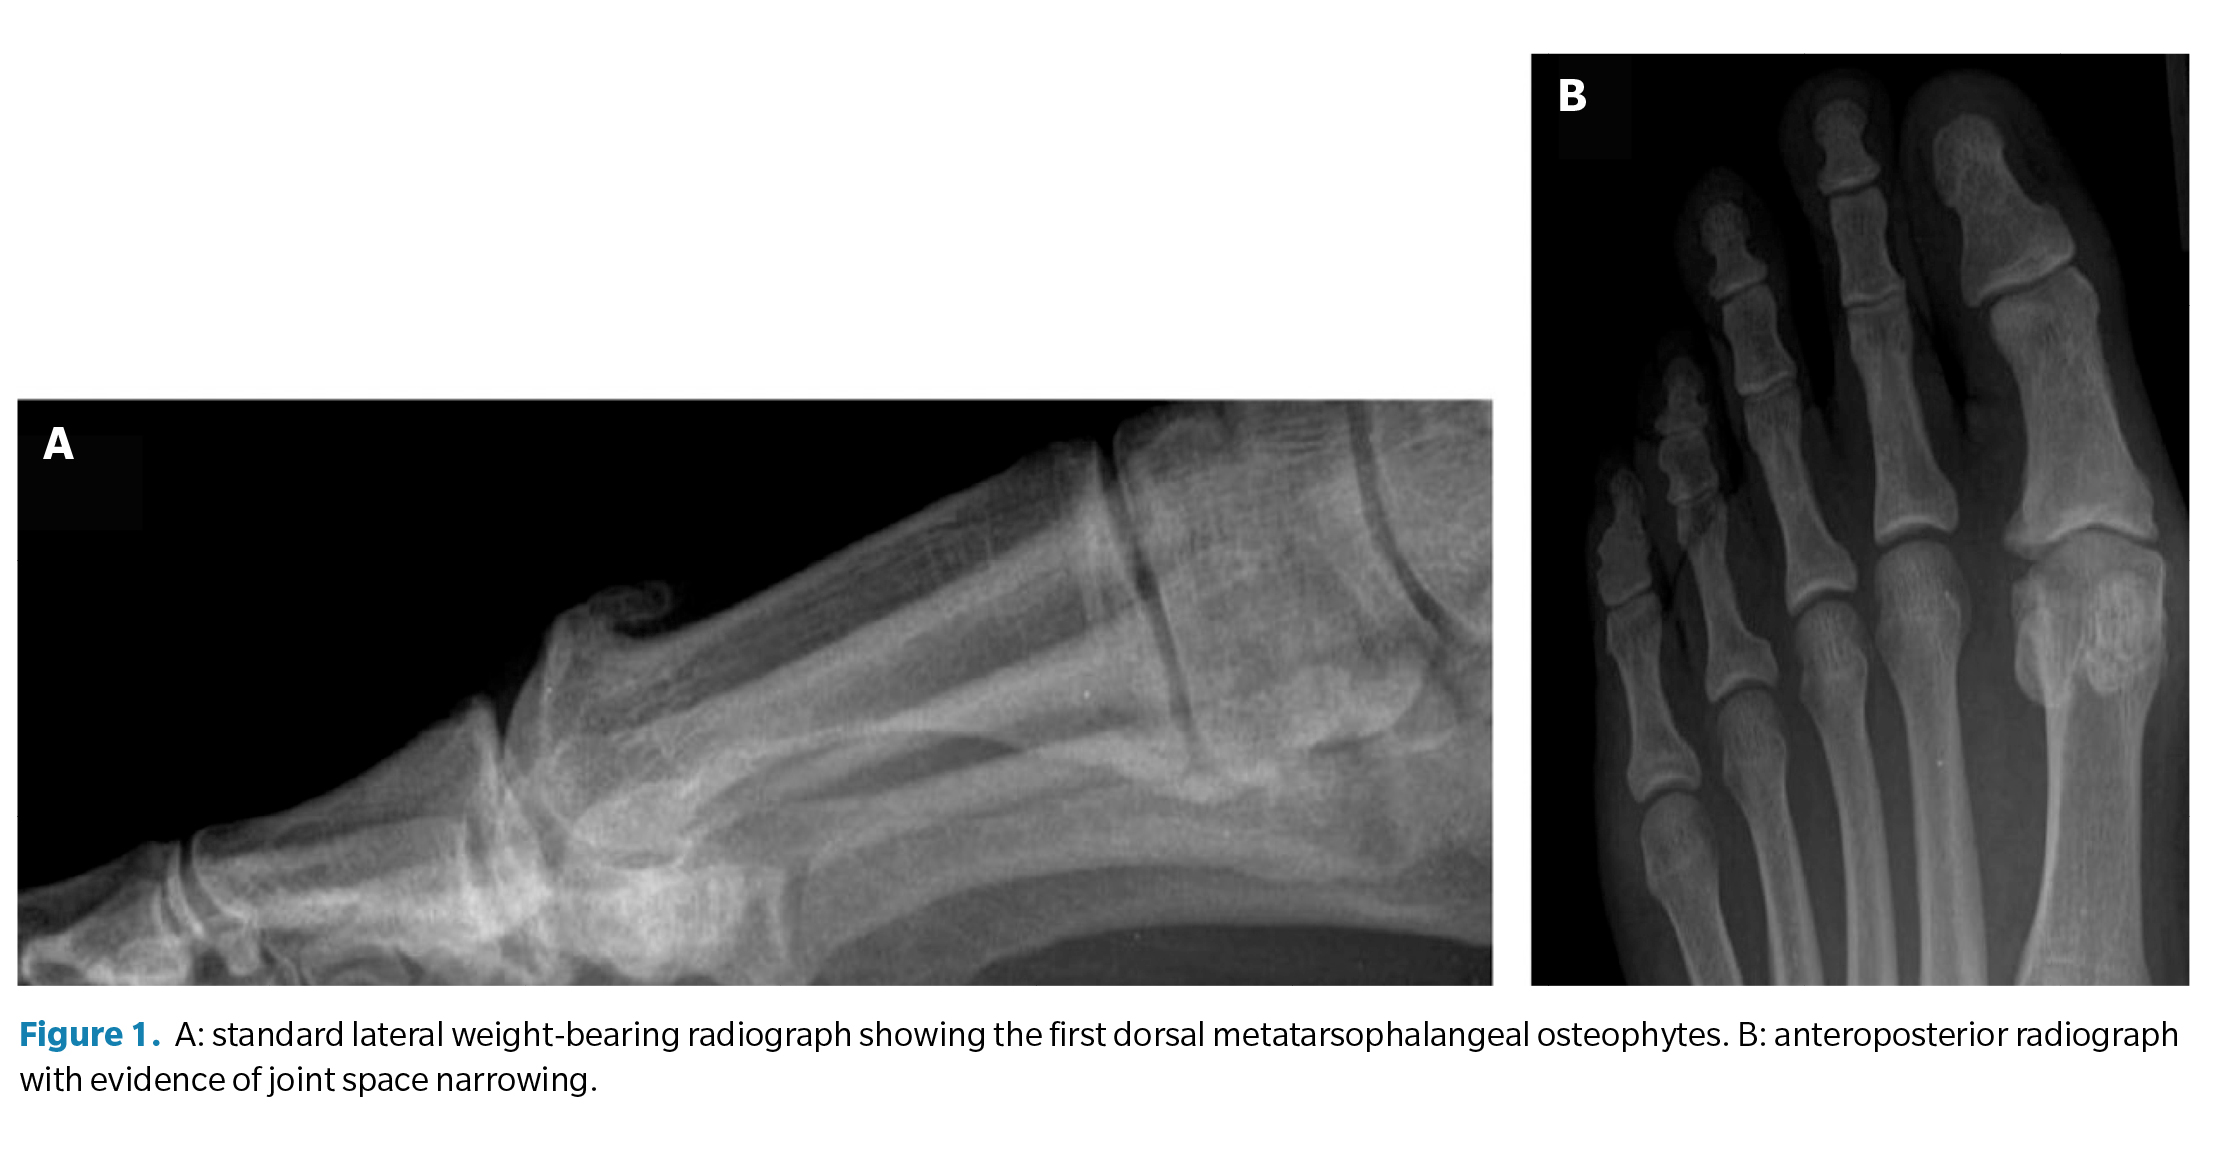

Radiological evaluation of HR is based on an anteroposterior and lateral weight-bearing radiograph (Figure 1). These imaging tests inform surgical decision-making, focusing on joint preservation techniques (cheilectomy), capital osteotomies, arthroplasties, or joint fusion techniques (arthrodesis) in more advanced cases. Lateral radiographs are recommended for identifying dorsal osteophytes and assessing the reduction of the first MTP joint space.